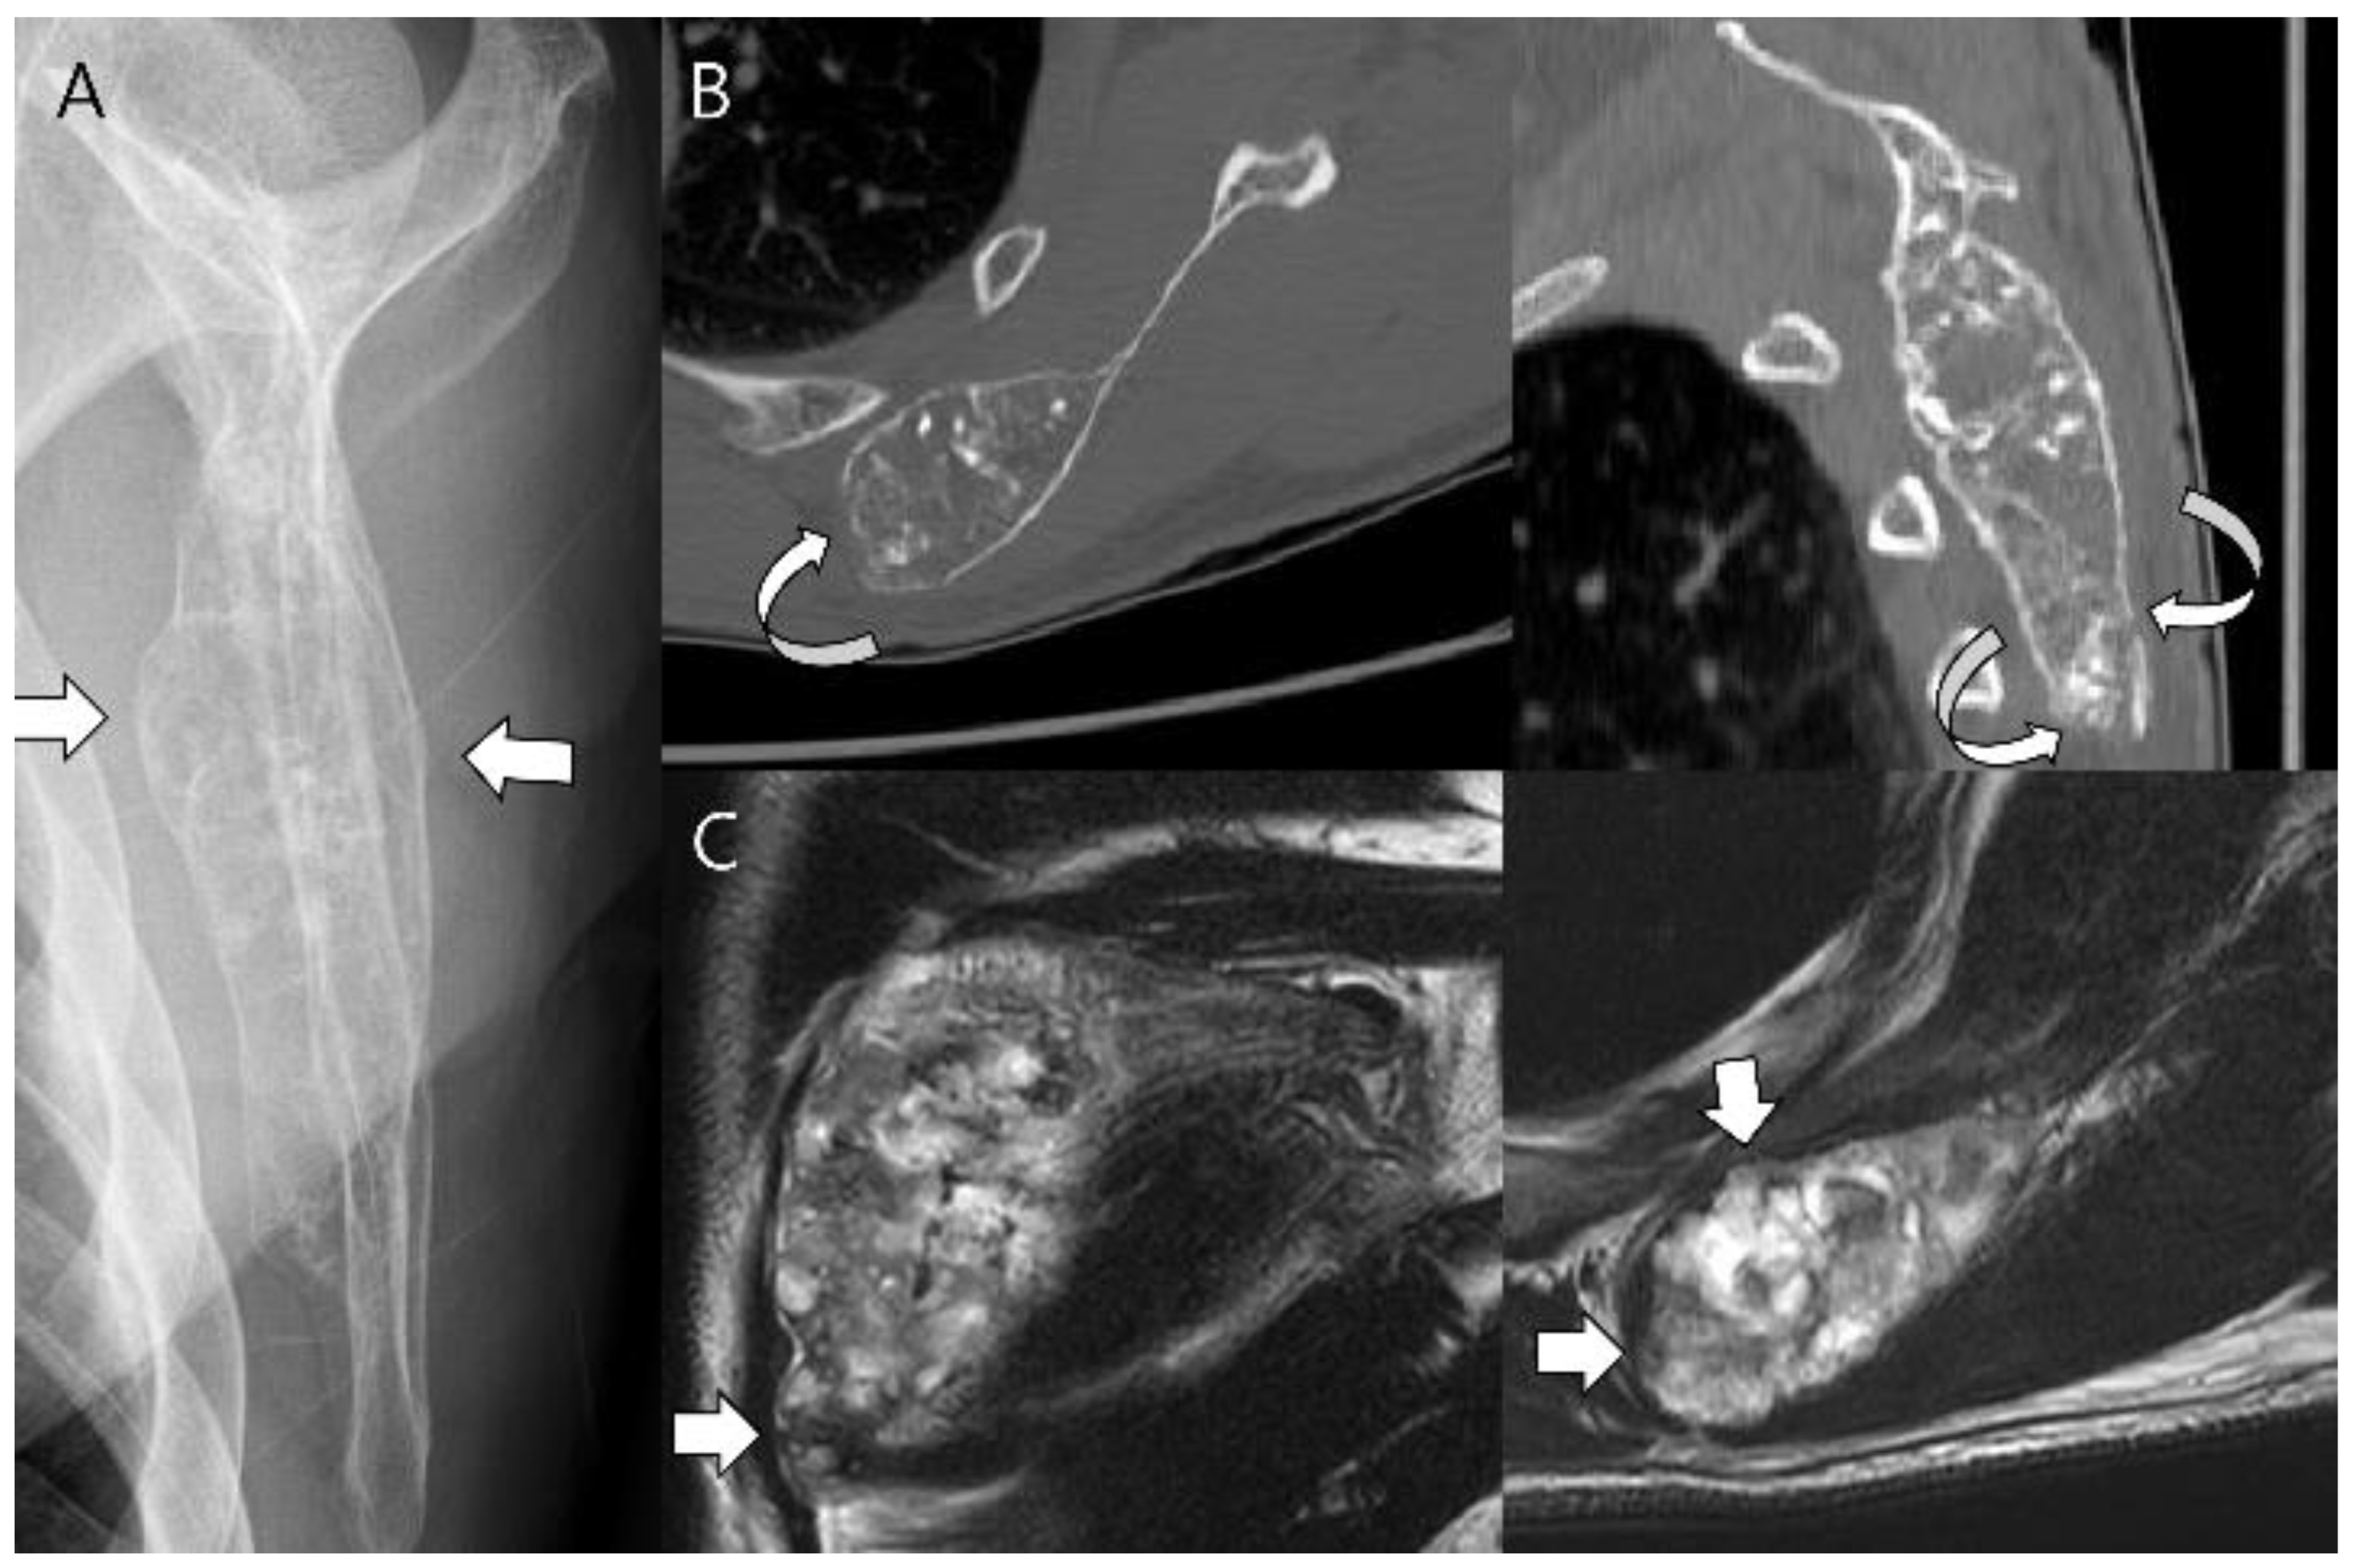

Figure 18.

Chondrosarcoma grade 2 of the scapula in a 58-year-old man. (A) Plain radiograph shows a lobulated intramedullary mass with chondral-type mineralization and bone expansion (arrows) in the scapular body. (B) Axial and sagittal CT scans show a large intramedullary mass with cortical destruction (curved arrows). (C) Coronal and axial T2-weighted images show focal extraosseous soft tissue masses (arrows).